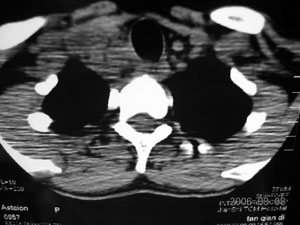

多发肿大淋巴结,呈环形持续性较明显强化,部分相互融合,结合临床,考虑炎性.

中心性坏死,环行强化支持:(1 淋巴结核)(2 脓肿) 临床高热,后者可能性更大 。神经鞘膜瘤不会广泛弥漫性的延续至上纵隔。